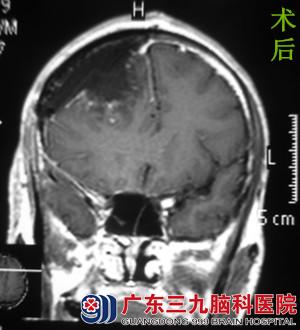

为进一步治疗,阿成一家人来到广东三九脑科医院,经头颅MR检查提示:右侧额部示团块状异常信号影,大小约44.4*48.9*51.7mm,考虑脑膜瘤可能性大。完善相关检查后,由综合神经外科的鲁明主任主刀,在全麻下行右侧额部脑膜瘤切除术。术中见白色肿瘤,质中、包膜完整,予镜下肿瘤全切,手术顺利结束。经专科治疗,患者康复出院。术后病理结果:过渡型脑膜瘤(WHO I级)。